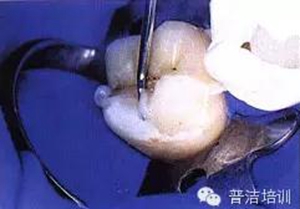

九、準(zhǔn)備口內(nèi)戴入

十、試戴樹(shù)脂高嵌體